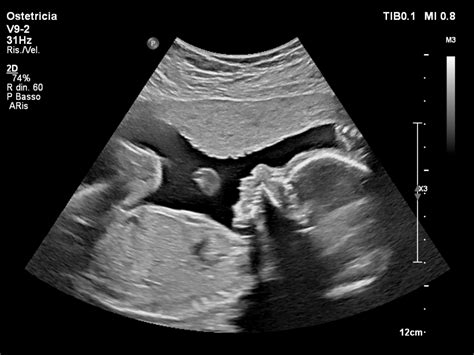

In alternativa alla palpazione addominale, si può procedere anche con ultrasuoni, test ormonale o raggi X. Ti consigliamo di recarti dal veterinario con il tuo pet per l’esame ecografico, che andrà fatto a circa 3 - 4 settimane dal calore, se non conosci con certezza il giorno in cui è avvenuto l’accoppiamento (o hai soltanto un sospetto). Un altro modo per controllare la gravidanza del tuo cane è quello di eseguire una Radiografia quando il processo gestazionale è più avanzato, a partire dal 50° giorno di gestazione.